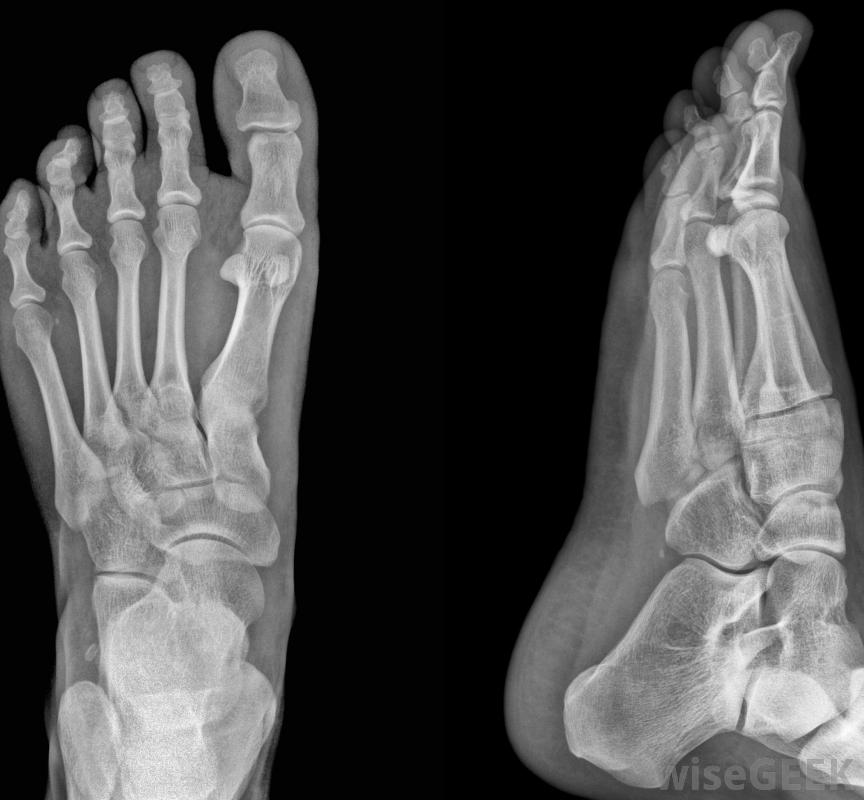

气枪用于稳定骨折,可通过x光片确认。